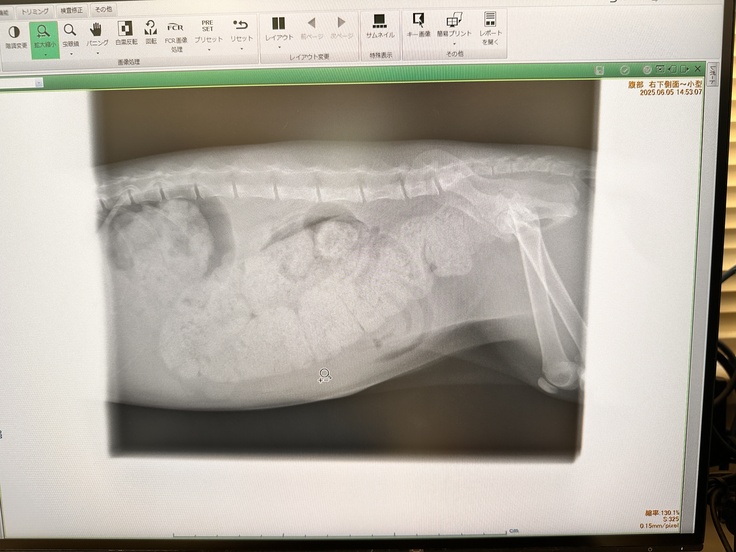

これがその時のレントゲンになります

お腹の中全部が💩なのが分かります

そして太くなってしまった腸管は元には戻らないとの事

膀胱は空っぽだけど、腸が便で埋まっている